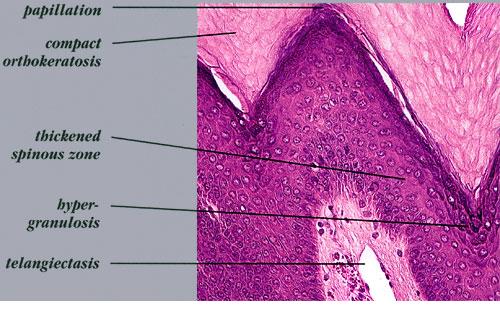

Nevus verrucosus = وحمة ثؤلولية